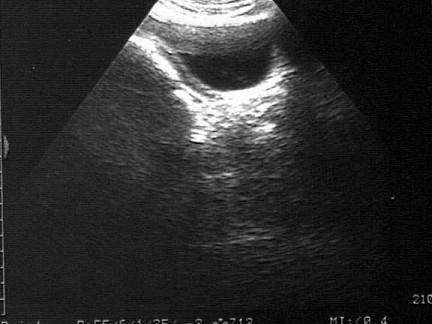

问题 女性,18岁,月经不来潮就诊。超声检查如图,最可能的诊断为?(?)

选项 A.畸胎瘤 B.先天性无子宫 C.子宫肌瘤 D.双子宫 E.始基子宫

答案 B